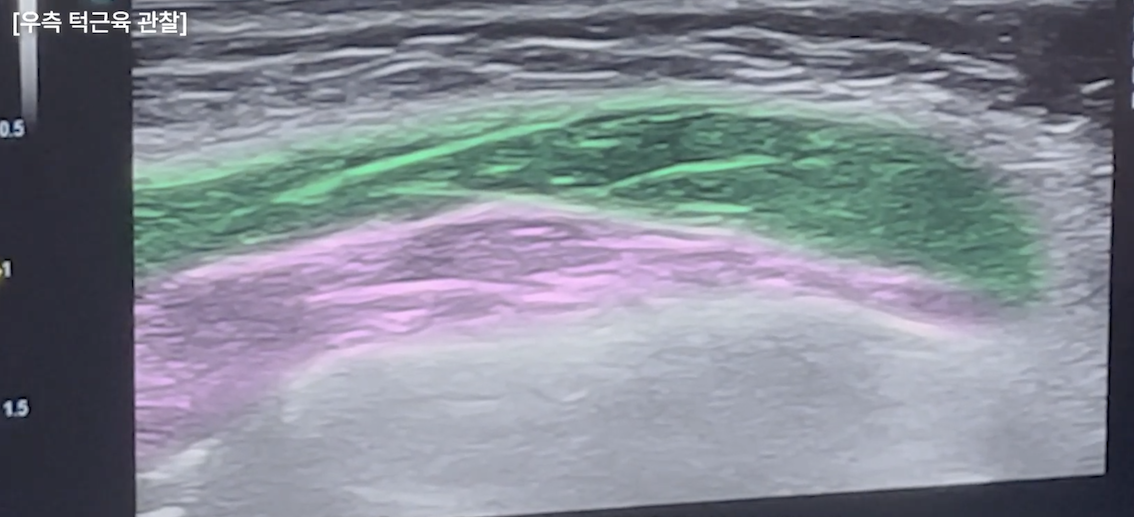

앞서 설명드렸듯 교근은 총 세 겹의 근육층으로 이루어져 있습니다.

이를 꽉 물어보게 하면 어떤 층이 주로 작동하는지가 드러나는데, 이 차이는 손으로 만져서는 정확히 알기 어렵고 초음파로 직접 확인해야 명확해집니다.

거기에 턱 근육의 윗부분(광대부위)의 경우에는 턱 근육 위를 침샘(귀밑침샘)이 덮어 더욱더 볼륨을 형성하는 경우도 있기 때문에 초음파로 정확한 원인을 확인 후 시술하는 것이 중요합니다.

천안 닉스의원에서는 초음파를 통해 가장 힘이 집중되는 근육의 핵심 포인트를 확인한 뒤, 그 지점을 정확히 겨냥해 시술을 디자인합니다.

또한 좌우 교근의 두께를 비교함으로써 어느 쪽에 용량 조절이 필요한지 판단할 수 있고, 정면에서 얼굴 한 쪽이 더 커 보이는 이유 역시 구조적으로 설명하고 교정할 수 있습니다.